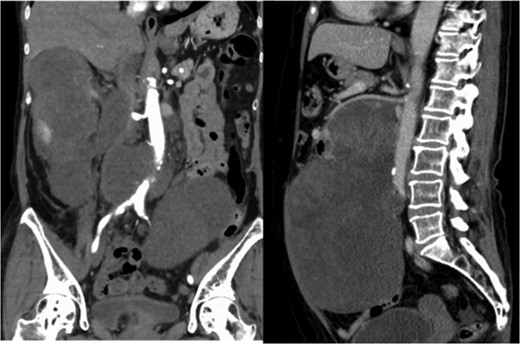

A 60-year-old female visited a clinic because of abdominal distension. She noticed abdominal distention one year prior to her clinical visit, but she left it for a year. Gradual enlargement of the mass eventually made her decide to see a doctor. Enhanced abdominal computed tomography (CT) revealed large retroperitoneal tumors. Mini-laparotomy and tumor biopsy confirmed her diagnosis as dedifferentiated liposarcoma, then she was referred to us for further examination and treatment. A multidetector CT scan revealed a hypodense mass in the retroperitoneum, with a size of ~30 × 20 cm2. The tumor appeared to invade the duodenum, head of the pancreas, right kidney, IVC and abdominal aorta (Fig. 1). The IVC was almost occluded by the tumor, but venous return from the lower extremities beyond the tumor was observed through collateral veins around the tumor (Fig. 2). The tumor invaded the abdominal aorta just below the left renal artery to the common iliac artery bifurcation, although the root and entire length of SMA appeared to be free from the tumor (Fig. 3). She underwent en bloc resection of the RL with resection of the right kidney, duodenum, head of the pancreas, a portion of the inferior IVC and abdominal aorta. Ax-F & F-F bypass was performed for vascular reconstruction using poly-tertrafluoroethylene (PTFE) to maintain the blood flow to the both lower extremities (Fig. 4). The lower abdominal aorta and both sides of common iliac arteries were resected with the tumor. The proximal stump of the abdominal aorta was closed with a running suture and covered by the omentum. The IVC was resected from just below the left renal vein to the common iliac veins. Reconstruction of the venous system including IVC and common iliac veins was not performed because venous collateral pathways had already developed sufficiently. Child’s reconstruction was performed after pylorus-preserving pancreatoduodenectomy. The duration of the surgery was 19 h 22 min, and blood loss was 4 811 mL, requiring 1680 mL of red blood cell transfusion. The tumor was 33 × 20 × 13 cm3 in size, weighed 4800 g, and had a fibrous capsule (Figs 5 and 6). Pathological examination revealed a dedifferentiated liposarcoma with negative margin (Fig. 7). Tumor invaded the pancreatic capsule, the renal capsule, the adventitia of the IVC and the abdominal aorta and infiltrated into the muscularis propria and focally into lamina propria of the duodenum. Edema of the both lower extremities was noted as postoperative complication, but that was gradually resolved by diuretics. The patient was discharged 37 days after surgery without serious postoperative complications such as pancreatic fistula, as well as graft infection or obstruction of two bypasses. Currently, she remains alive and well with no evidence of recurrence at 16 months post-operation.

Multidetector CT scan (coronal view). The tumor invaded the IVC from the orifice of the right renal vein and the peripheral IVC was almost fully occluded.